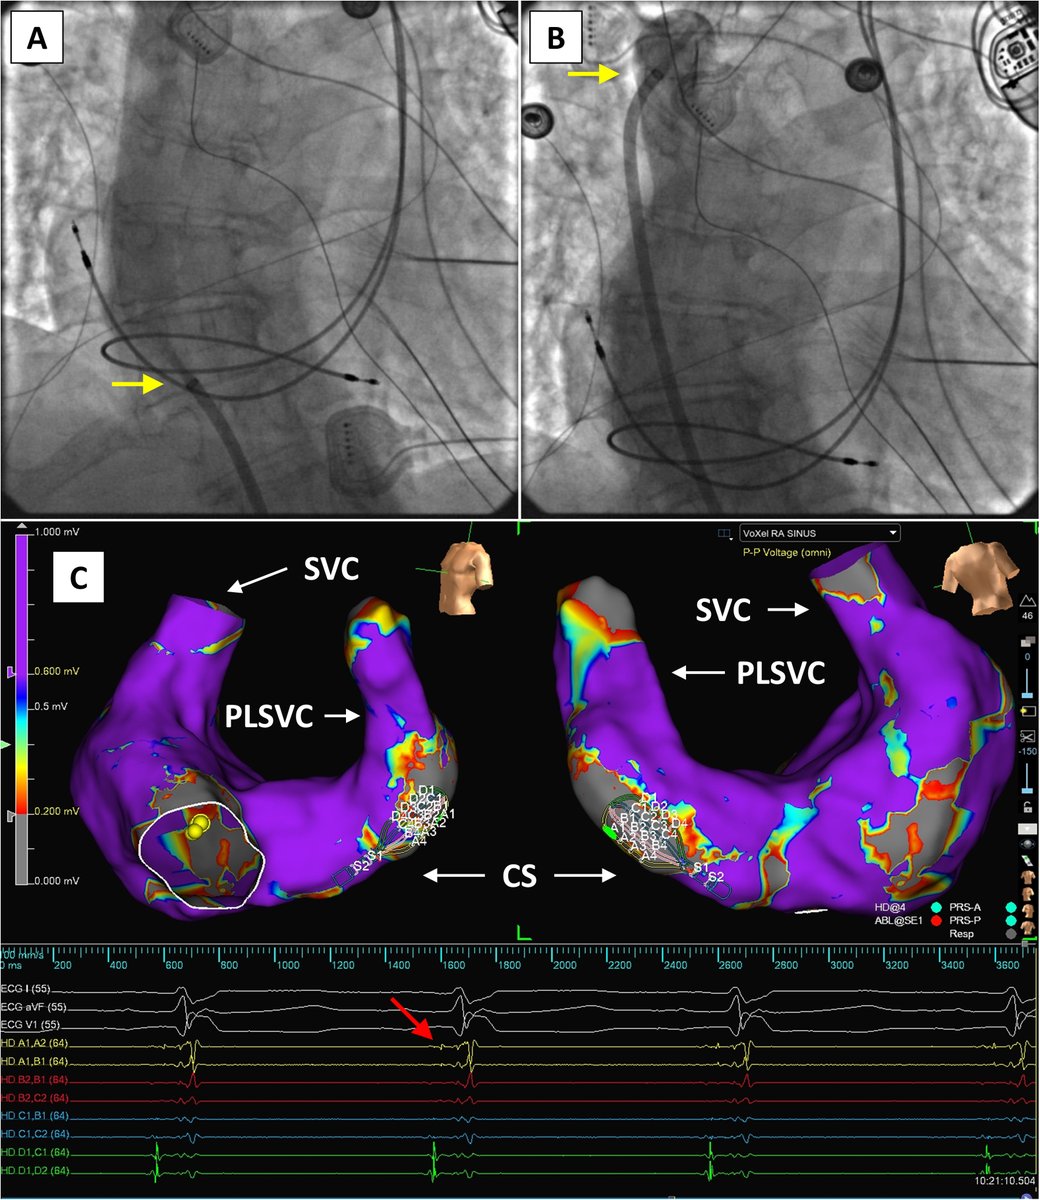

Pulsed field ablation in persistent left superior vena cava for atrial fibrillation via interrupted inferior vena cava with azygos continuation utilizing novel electroanatomic mapping features in the presence of a permanent pacemaker Norman C. Wang, MD, MS heartrhythmcasereports.com/article/S2214-…

Pulsed field ablation in persistent left superior vena cava for atrial fibrillation via interrupted inferior vena cava with azygos continuation utilizing novel electroanatomic mapping features in the presence of a permanent pacemaker